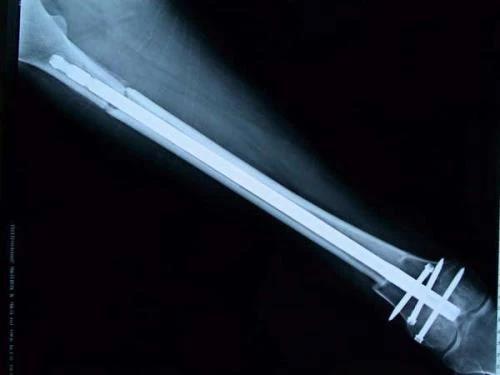

新輔助化療的目的是盡早殺滅遠(yuǎn)處微小轉(zhuǎn)移灶,縮小腫瘤及周圍炎性水腫反應(yīng)區(qū),以利于后續(xù)的保肢手術(shù);觀察腫瘤對(duì)化療的敏感性,為進(jìn)一步指定個(gè)體化的術(shù)后化療方案奠定基礎(chǔ)。骨肉瘤新輔助化療下的保肢治療如下圖所示: